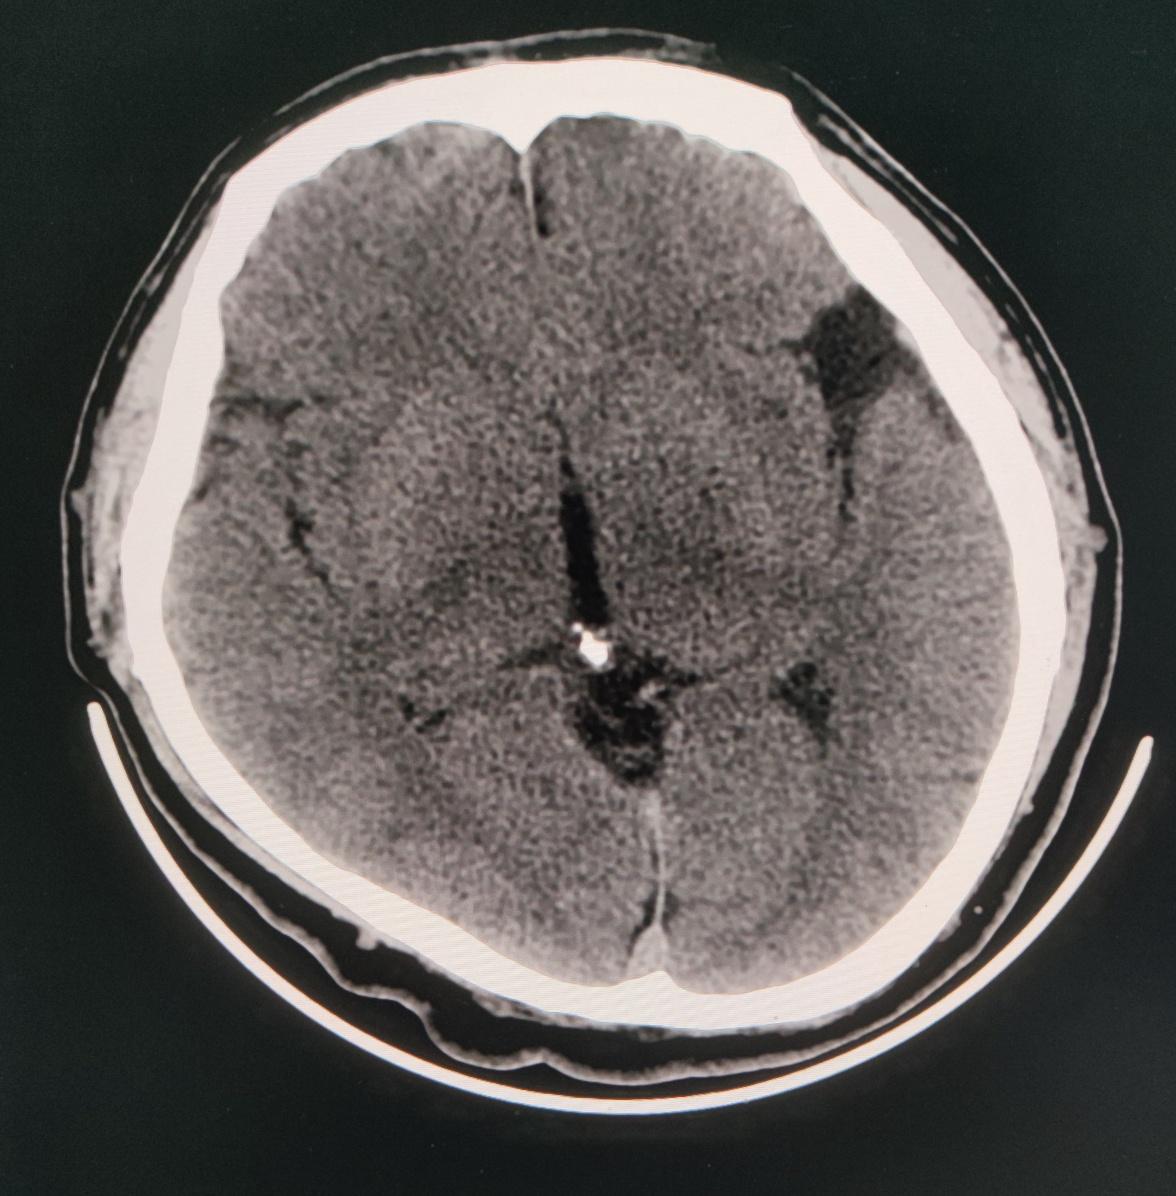

头颅ct示左侧侧裂池少许高密度影,蛛血?

左侧裂池内高密度影,请会诊

发病时颅脑ct显示前纵裂池,侧裂池,环池可见积血.